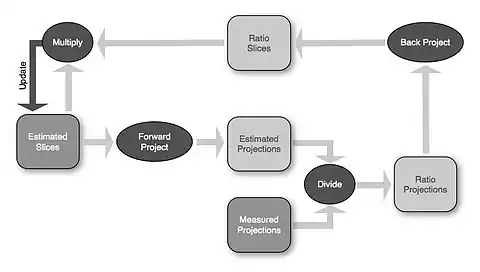

- The reconstruction process is illustrated in Figure 7.15.12 for a simple image consisting of a 2x2 pixel matrix. It starts with a guess of a solution and then compares the actual projections with the ones obtained on the basis of the guess. Modifications are made to the pixel values and the procedure is repeated. Repetitive iterations are made until the differences between the measured and calculated projections are insignificant.

- The first estimate of the image matrix is made by distributing the first projection, P1, evenly through an empty pixel matrix. The second projection, P2, is then compared to the same projection from the estimated matrix and the difference between actual and estimated projections is added to the estimated matrix. The process is repeated for all other projections.

- Many of these computations are based on the Maximum-Likelihood Expectation-Maximisation (ML-EM) algorithm where a division process is used to compare actual and estimated projections, as shown below:

- One cycle of data through this processing chain is referred to as one iteration. The Ordered-Subsets Expectation-Maximisation (OS-EM) algorithm can be used to substantially reduce the computation time by utilising a limited number of projections (called subsets) in a sequential fashion within the iterative process. Noise generated during the reconstruction process can be reduced, for example, using a Gaussian filter built into the reconstruction calculations or applied as a post-filter: